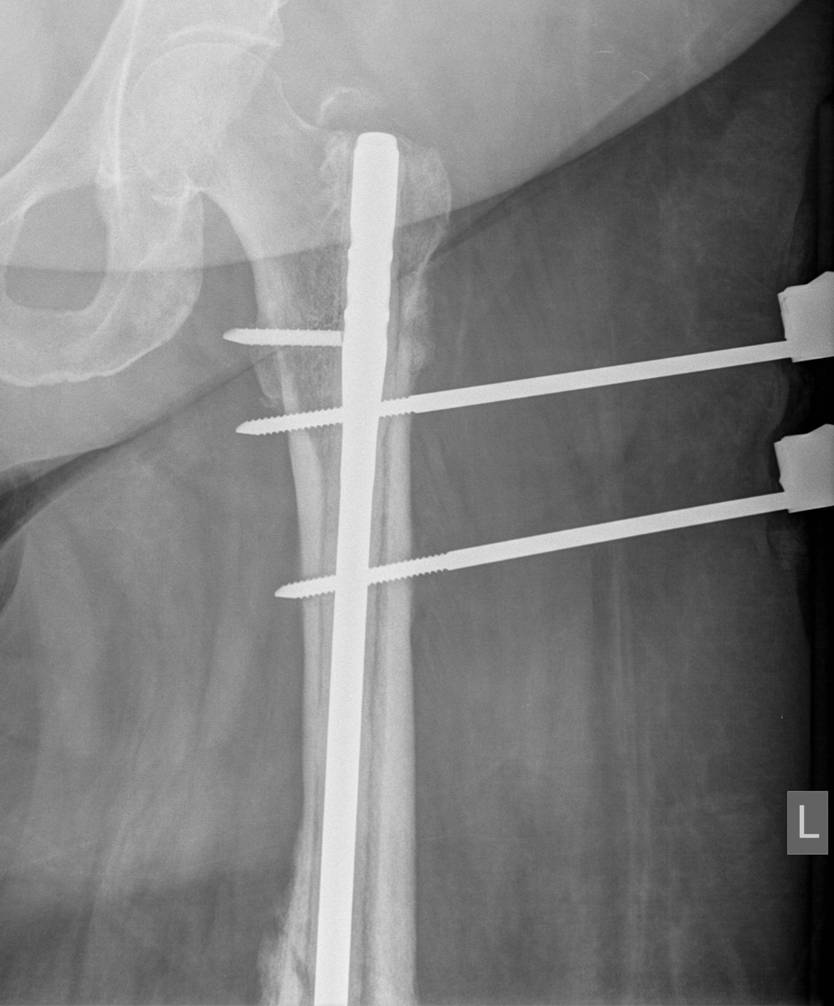

1. External fixation

Indications

- severely contaminated wound

- Damage Control Orthopaedics

- complex femoral fracture with vascular injury

AO Surgery Technique

- safe zone is lateral

Timing of conversion to IMN

Harwood et al J Orthop Trauma 2006

- two groups

- 81 patients treated with early IMN

- 111 patients treated with external fixation converted to IMN at mean of two weeks

- at time of surgery, pin sites excised, washed, and overdrilled

- no difference in deep infection rates between two groups

https://pubmed.ncbi.nlm.nih.gov/16648699/